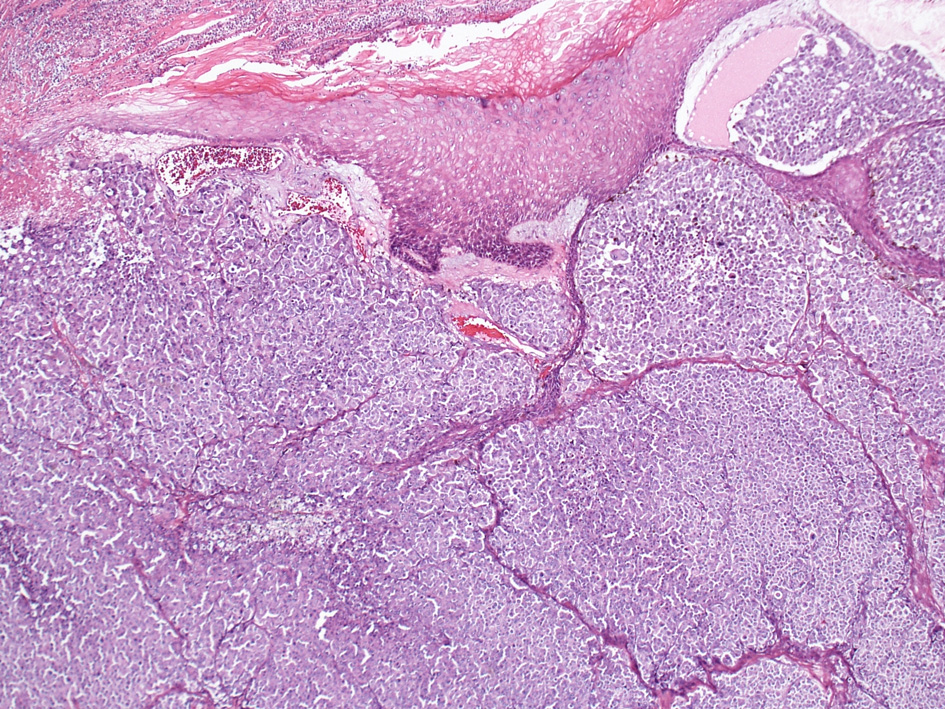

Case: 結節型悪性黒色腫†

66years-old female 頭皮。

HE lpf

- 組織学的に表皮内の水平方向への増殖はないか、あってもごくわずかである。

- 真皮内病巣は通常好酸性から淡明豊かな細胞質をもつ卵円形ないし円形の類上皮細胞から構成されている。細胞異型度と核分裂像は症例によりさまざま。